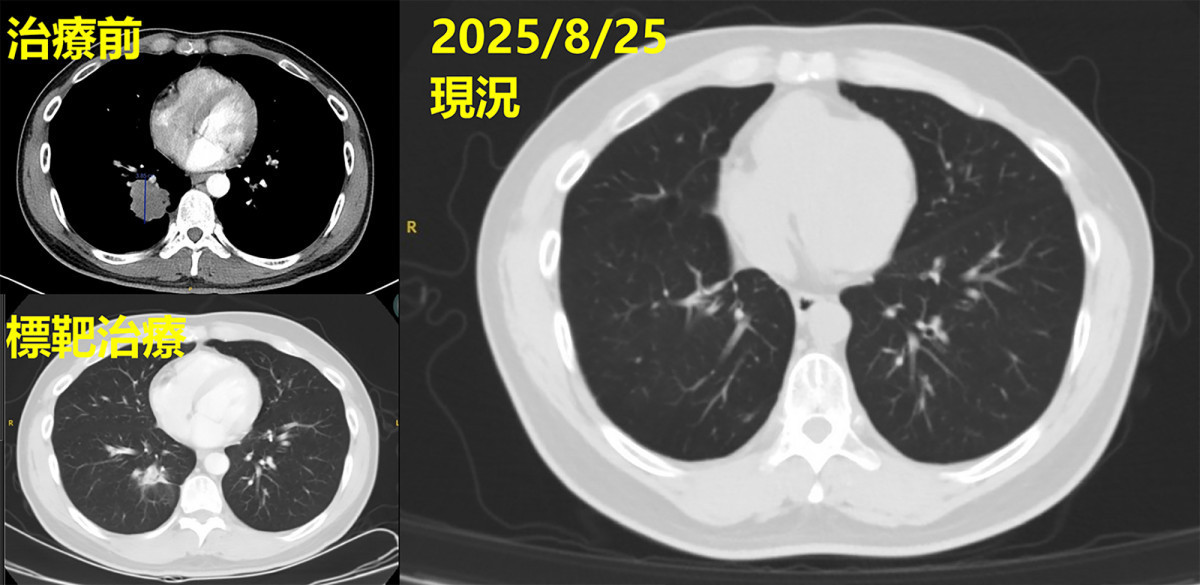

許先生入院後初步檢測未發現可用突變,後續在彰基協助下參與國家衛生研究院臨床試驗,最終確認帶有EGFR exon

19 deletion突變,得以使用第三代標靶藥物。治療一段時間後,影像顯示腫瘤由4公分縮小至2.8公分,控制成效顯著。

經治療後影像追蹤可見,原近4公分腫瘤明顯消失,病情獲得良好控制。圖/彰基醫院提供